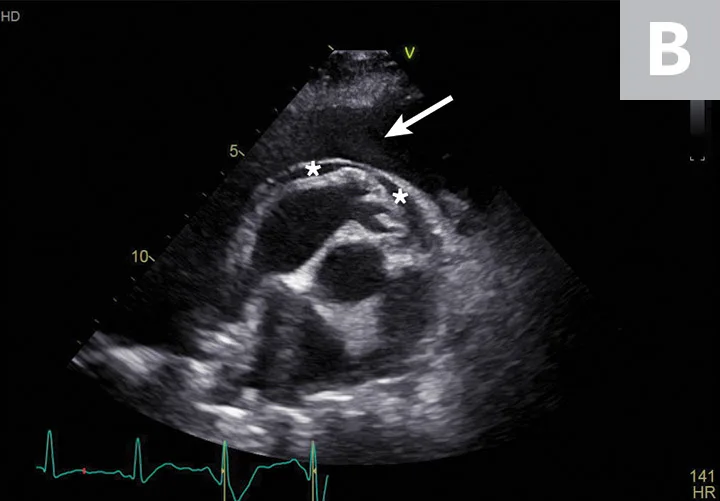

3. Abdominal Mass Identification in the Liver & Spleen

Hepatic and splenic nodules or masses can be primary or metastatic; can be benign or malignant; and may appear as a single mass, multiple masses, or diffusely infiltrative.10,11 Operator skill level, resolution of the ultrasound transducer, and echogenicity of the surrounding parenchyma can impact detection of soft-tissue nodules.12 Common malignant hepatic and splenic neoplasms include hepatocellular carcinoma, hemangiosarcoma, lymphoma, and histiocytic sarcoma. Common benign changes in the liver and spleen include hyperplasia, myelolipoma, hematoma, lymphoid hyperplasia, and extramedullary hematopoiesis.12,13 A large hepatic mass and peritoneal effusion are more often associated with neoplasia than a benign growth in the liver.13 In the spleen, nodules 1 to 2 cm in diameter, multiple targetoid lesions (hyperechoic center with hypoechoic rim), and peritoneal effusion are associated with neoplasia.14 Hepatic and splenic masses can have diverse characteristics, including well- or poorly circumscribed margins, variable echogenicity, fluid cavitation, and mineralization (Figure 3).

FIGURE 3

Transverse image of the right liver in a dog with a hyperechoic and multicavitary liver mass (A; asterisk) adjacent to a normal portion of liver (arrow). Deep (ie, bottom of the image) to the liver and the mass, the diaphragm appears as a hyperechoic line. Hypoechoic mass (B; asterisk) protruding from the splenic capsule.